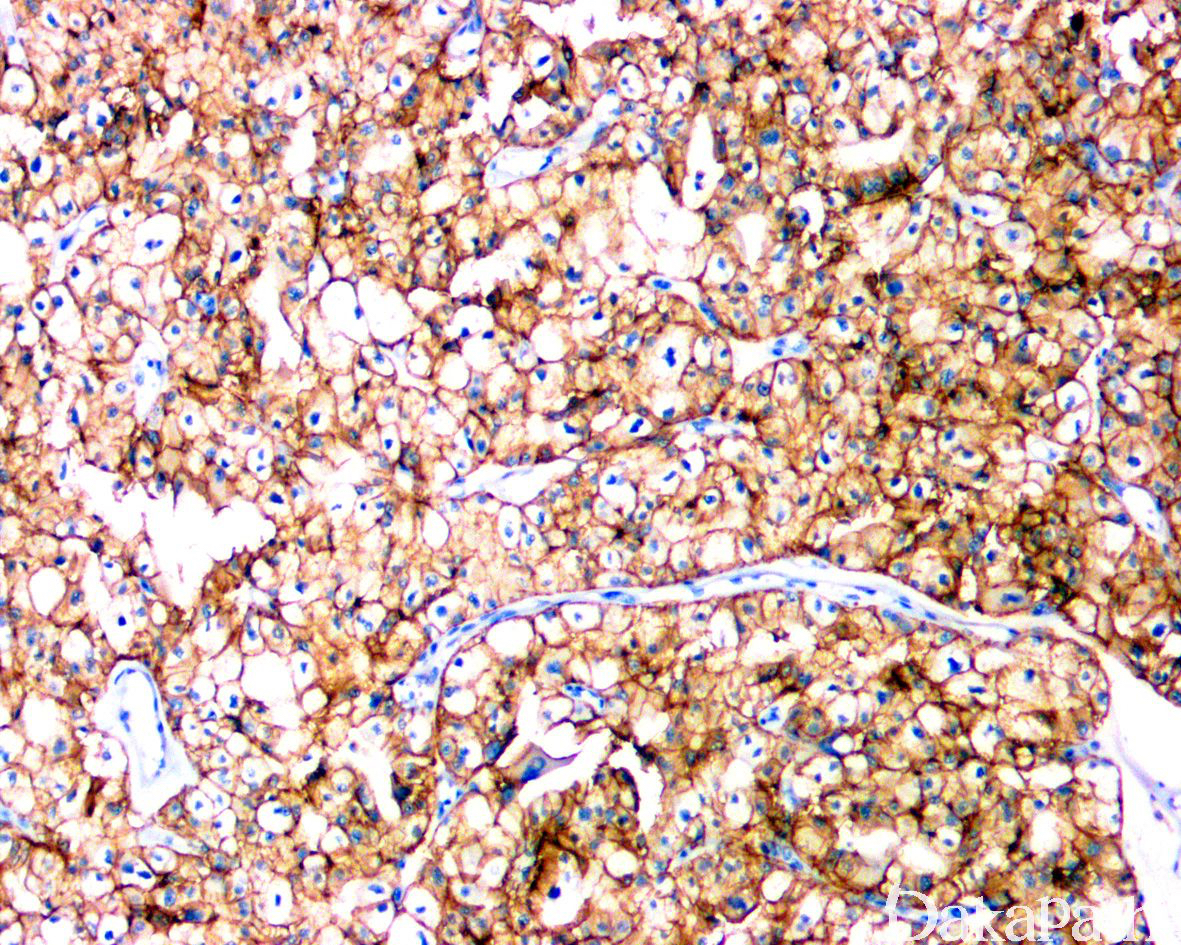

嫌色性肾细胞癌的癌细胞大而浅染,细胞膜非常清楚,核皱褶伴核周空晕。

肿瘤边界清楚,无包膜,周围可见内陷的良性肾小管,瘤细胞特征性排列成实性片状,隔以不完全的玻璃样变血管间隔;其他结构包括小的巢状、微囊性、梁状,偶尔局灶呈乳头状,少数病例可见管状结构;

细胞典型特征是体积大,包膜清楚,胞浆网状淡染;

部分病例呈嗜酸细胞变异型,表现为以具嗜酸性颗粒状胞浆的小细胞为主,这两种细胞常混合存在,嗜酸性细胞排列在细胞巢或片中央,淡染细胞排列在周围;

细胞核常显示清楚的不规则皱褶(葡萄干样),染色质粗,常见双核和核周空晕;

PAX8. CD117. parvabumin、E-cadherin、CK7 阳性(CK7 在嗜酸细胞嫌色细胞肾细胞癌中可能仅为局灶阳性),部分病例表达 GATA3,偶尔可表达神经内分泌标志物如 Syn 等,胶体铁弥漫胞浆染色。SDHB 表达无缺失。vimentin、CD10 膜、CA9 阴性(CD10 可表现为胞浆染色阳性)。